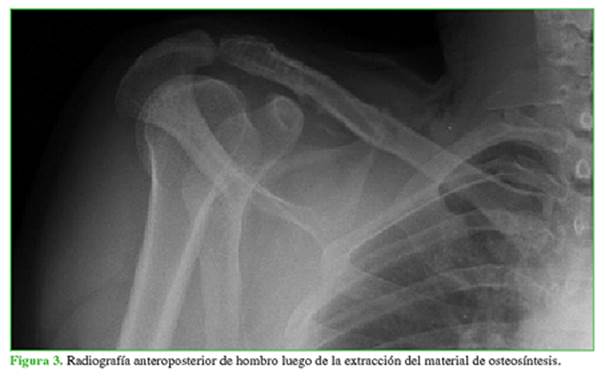

A los seis meses de la cirugía, comenzó con un dolor limitante y creciente en el hombro derecho, por lo que decidió consultar, en esa oportunidad, en nuestra institución. En el examen físico, se detectó hipersensibilidad a nivel de la apófisis coracoides con impotencia funcional del hombro debido al dolor severo, 9/10 en la escala analógica visual. Se tomaron radiografías de clavícula y hombro, de frente, de perfil y proyección de Zanca, en las que se observó la erosión de la apófisis coracoides causada por el contacto del extremo distal del tornillo de cortical utilizado en la placa bloqueada de compresión (Figura 1). Se decidió realizar una tomografía computarizada tridimensional para evaluar correctamente la extensión de la lesión (Figura 2).